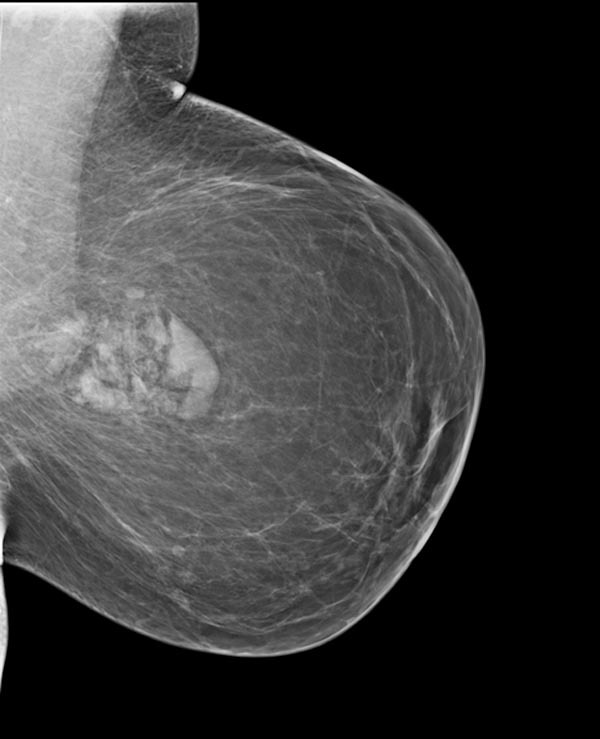

What are the characteristic mammography findings of a hamartoma?

An involuting fibroadenoma